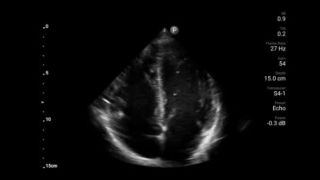

Keep an eye on COVID pneumonia

Lumify can help give results similar to a chest CT when evaluating pneumonia and adult respiratory distress syndrome.

Lumify S4-1 broadband phased array transducer

Intro to transthoracic echocardiography